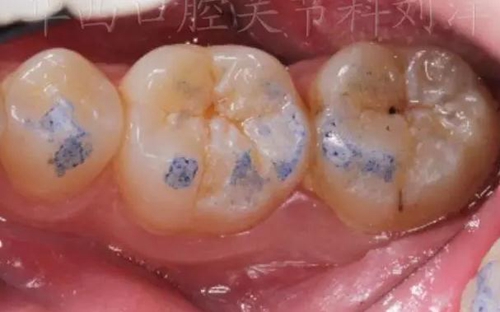

①先用100微米做粗調(diào)

▲ 圖1:100µm咬合紙

▲ 圖2:100µm咬合紙的效果